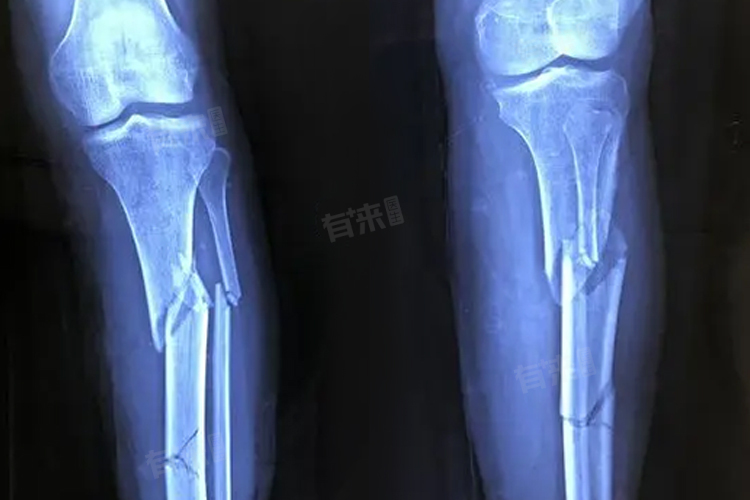

1、拍片方式:常见的拍片方式有X光片、CT扫描和磁共振成像,X光片是骨折初步检查的常用手段,费用一般在80-150元。CT扫描能更清晰地显示骨折细节及周围组织情况,价格通常在200-500元,磁共振检查对骨折后的软组织损伤评估更准确,费用大概在500-1000元,应根据骨折的具体情况选择合适的拍片方式。

2、医院等级:不同等级的医院收费标准有所不同。基层医院如社区医院或乡镇卫生院,X光片费用可能在50-100元,CT扫描约150-300元。而在大型三甲医院,X光片费用约100-200元,CT扫描可能在300-600元,患者可根据自身需求和经济状况选择合适的医院。

3、地区经济水平:经济发达地区的医疗费用相对较高,在一线城市,X光片可能需要150-200元,CT扫描在400-600元。而在经济欠发达地区,费用会相对较低。如中西部地区,X光片可能80-120元,CT扫描200-400元。

4、设备性能:先进的拍片设备通常能提供更精准的图像,但费用也会略高,采用新型高端X光机拍摄,费用可能在100-180元,先进的CT设备扫描价格可能在400-800元,医院会根据自身的定位和患者需求配置不同性能的设备。

5、拍片部位及数量:如果需要拍摄多个部位或对同一部位进行不同角度的拍摄,费用会相应增加。如单独拍摄手腕部X光片约80-120元,若同时拍摄手腕和肘部,费用可能在150-250元,拍摄前应与医生充分沟通,明确拍摄的部位和必要性。